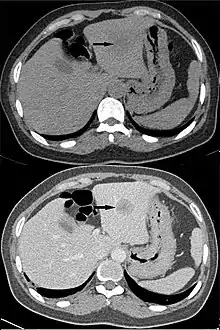

Hepatocellular carcinoma, without (top) and with (bottom) IV contrast.

"Washout" is where tissue loads radiocontrast during arterial phase, but then returns to a rather hypodense state in venous or later phases. This is a property of for example hepatocellular carcinoma as compared to the rest of the liver parenchyma.[3]